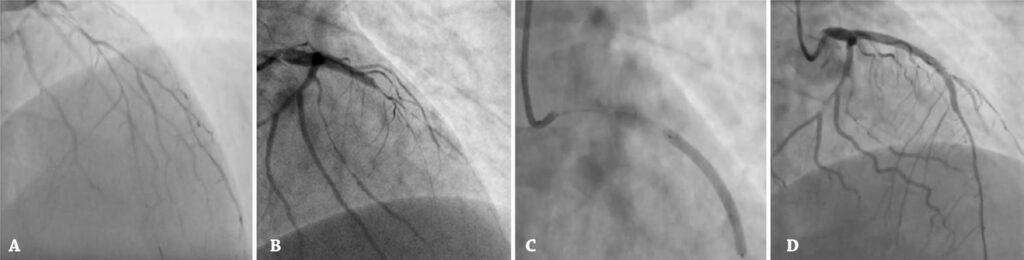

A rare cause of cardiac arrest: a case of an extensive left coronary artery spontaneous dissection

A 28-year-old male with a previous history of drug abuse was sent to an emergent coronary angiography, after a cardiac arrest, with a post-resuscitation eletrocardiogram showing ST-segment elevation from V1-V4. Angiography showed multivessel and multisegment spontaneous coronary artery dissection. Due to clinical instability, patient underwent left anterior descending artery percutaneous coronary intervention. Prevalence of spontaneous coronary artery dissection as the cause of acute coronary syndrome is anecdotal in men. Yet, in the right scenarios as in this case, it must be ruled out. Cardiorespiratory arrest is an uncommon presentation of spontaneous coronary artery dissection and percutaneous coronary intervention in spontaneous coronary artery dissection is still a matter of debate.